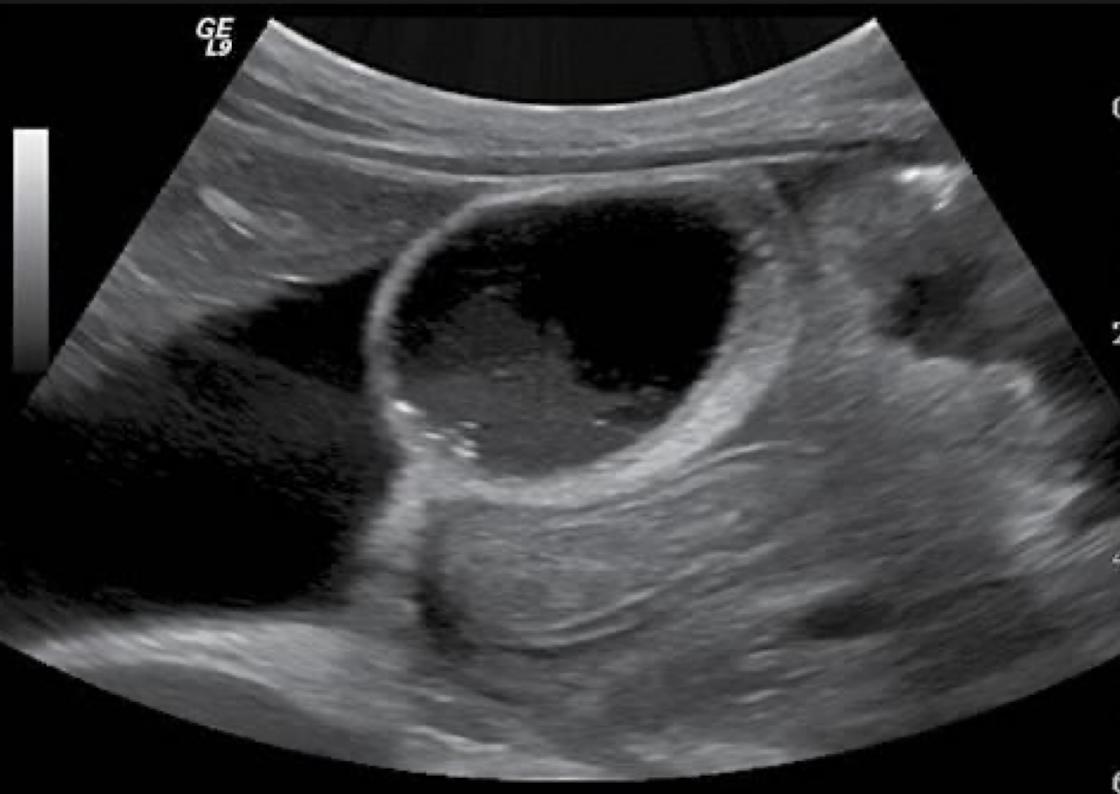

cholelithiasis

tiny stones along sludge layer + ascites